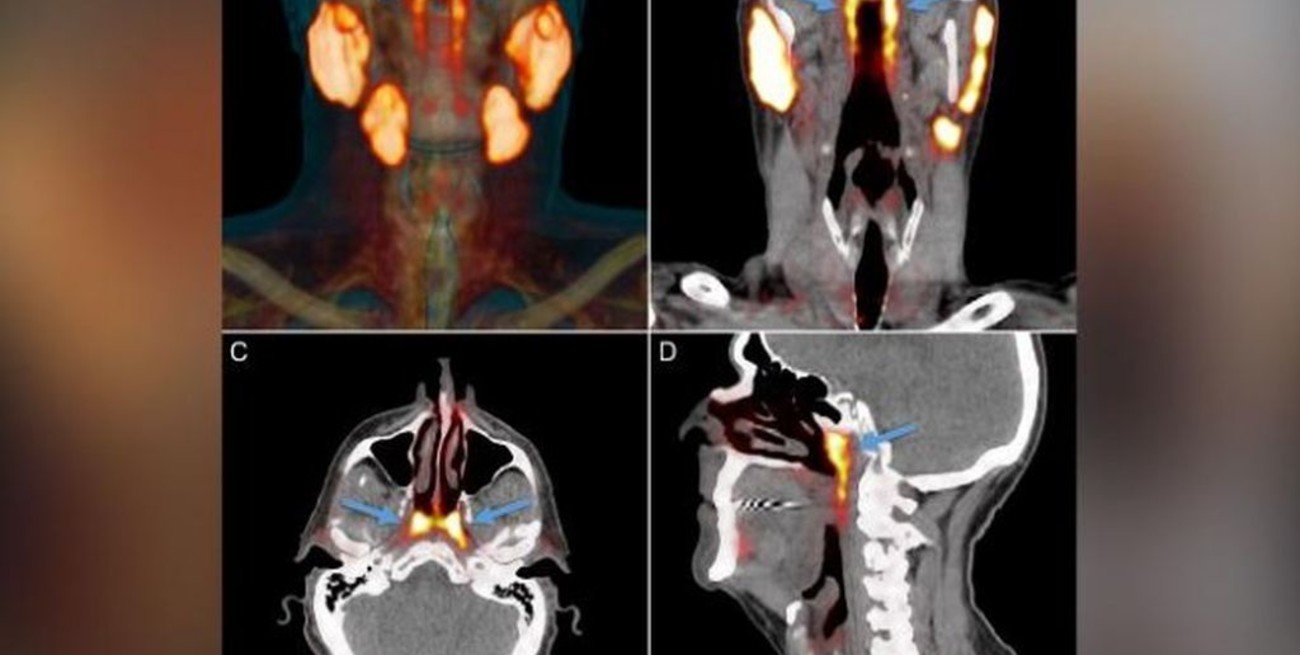

La «entidad desconocida» solo se identificó cuando los médicos utilizaban un tipo de exploración nuevo y avanzado llamado PSMA PET/CT que se ha utilizado para detectar la propagación del cáncer de próstata. PSMA PET es la abreviatura de la obtención de imágenes de antígeno de membrana específico de la próstata mediante tomografía por emisión de positrones. Las glándulas salivales se muestran claramente en este tipo de imagen altamente sensible . «Las personas tienen tres conjuntos de glándulas salivales grandes, pero no allí». Así dijo el autor del estudio Wouter Vogel, un oncólogo radioterapeuta del Instituto del Cáncer de los Países Bajos, en un comunicado de prensa en mayo.

«Hasta donde sabíamos, las únicas glándulas salivales o mucosas en la nasofaringe son microscópicamente pequeñas. Y hasta 1000 están distribuidas uniformemente por toda la mucosa. Así que imagina nuestra sorpresa cuando encontramos estas». Muchos grandes descubrimientos científicos «son una sorpresa, un hallazgo incidental». Dijo Joy Reidenberg, profesora de anatomía en la Escuela de Medicina Icahn en Mount Sinai en la ciudad de Nueva York, que no participó en el estudio. «Afortunadamente, estos investigadores estaban sintonizados con los datos y eran lo suficientemente expertos en anatomía como para notar el brillo inusual en una región que se pensaba que no contenía glándulas salivales», agregó Reidenberg por correo electrónico. «Como dijo una vez el famoso (fallecido biólogo francés) Louis Pasteur: ‘El azar favorece a la mente preparada'».